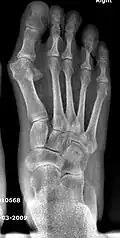

For recurrence correction after fusion procedure (Fig. 9) Metatarsus primus varus deformity and pain recurred 6 months after modified Lapidus procedure and it could also be again corrected by the syndesmosis procedure.